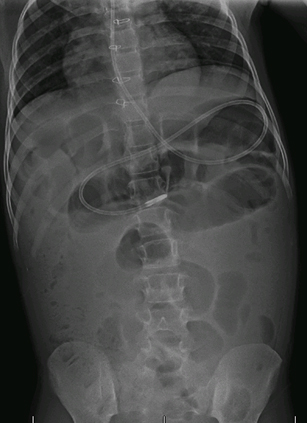

Radiografia abdominal simples (incluindo as incidências ortostática e em decúbito lateral [cross-table]): deve ser obtida em caso de suspeita de obstrução intestinal.[Figure caption and citation for the preceding image starts]: Radiografia abdominal mostrando impactação fecal em um paciente com constipaçãoDos acervos do Dr. R.A. Gomez-Suarez e Dr. J.E. Fortunato; usado com permissão [Citation ends].